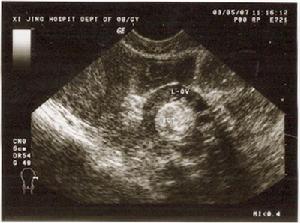

圖11.纖維瘤

(1)大體檢查:腫瘤多為單側雙側占4%~10%圓形、腎形或分葉結節狀。表面光滑,包膜完整,實性質地硬。切面實性,編織狀結構明顯,灰白或粉白色偶見出血或囊性變

(2)顯微鏡下檢查:瘤細胞長梭形,胞質少無脂滴。細胞排列緊密呈編織狀或席紋狀。膠原纖維豐富可伴有廣泛的玻璃樣變。瘤細胞無不典型形狀,亦無核分裂象(圖1)。